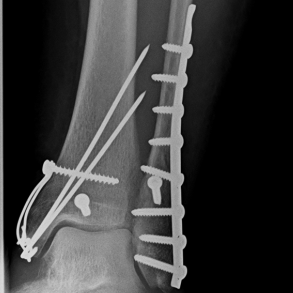

Röntgenbilder